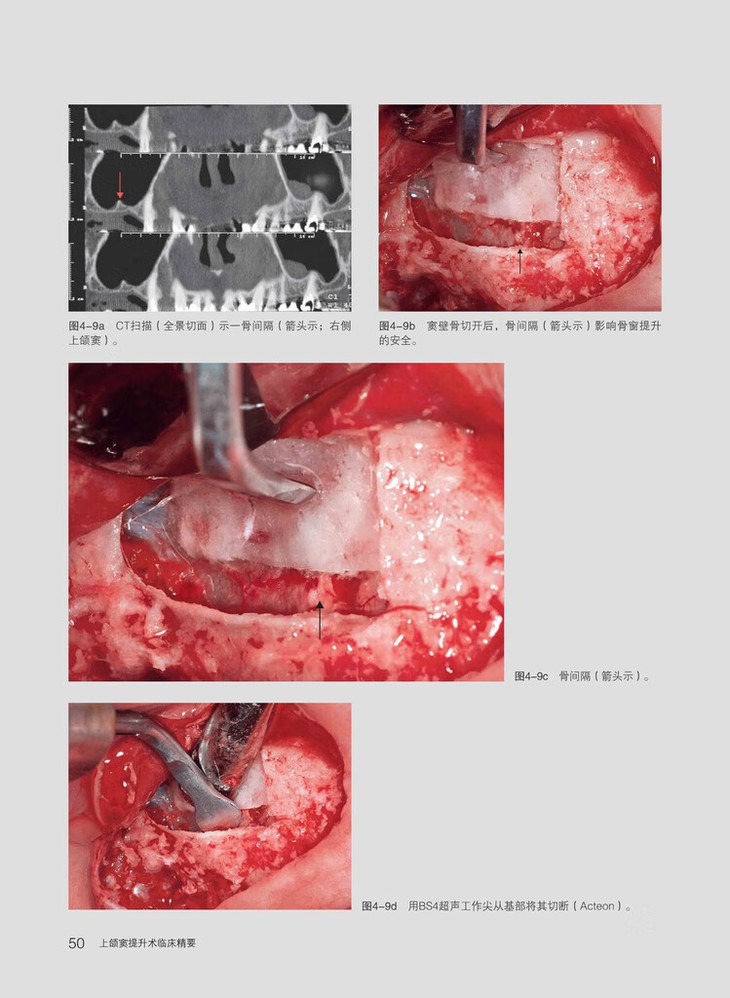

《上颌窦提升术临床精要》着重于解剖标志点的描述、常见的临床病例、新超声装置的应用以及可能的并发症。通过一步一步的临床照片,帮助读者在上颌窦提升手术中做出合理的临床决策以及解决可能的并发症。